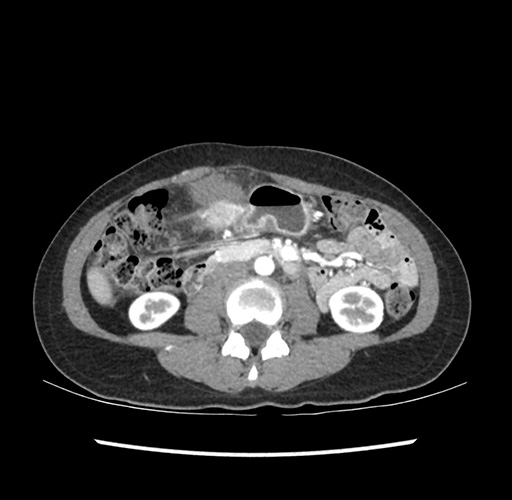

Imaging Analysis

Look through the patient's CT scan to identify any areas of concern for the necessary procedure.

Based on your CT findings, which issue(s) would give reason for "planned slowing down moment(s)" in this case?

Considering a standard left lateral sectionectomy procedure, what step(s) of the operation would you do differently in this case ?